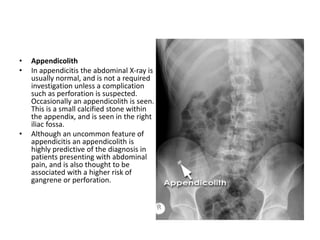

• Appendicolith

• In appendicitis the abdominal X-ray is

usually normal, and is not a required

investigation unless a complication

such as perforation is suspected.

Occasionally an appendicolith is seen.

This is a small calcified stone within

the appendix, and is seen in the right

iliac fossa.

• Although an uncommon feature of

appendicitis an appendicolith is

highly predictive of the diagnosis in

patients presenting with abdominal

pain, and is also thought to be

associated with a higher risk of

gangrene or perforation.

• Appendicolith • Inappendicitis the abdominal X-ray is usually normal, and is not a required investigation unless a complication such as perforation is suspected. Occasionally an appendicolith is seen. This is a small calcified stone within the appendix, and is seen in the right iliac fossa. • Although an uncommon feature of appendicitis an appendicolith is highly predictive of the diagnosis in patients presenting with abdominal pain, and is also thought to be associated with a higher risk of gangrene or perforation.